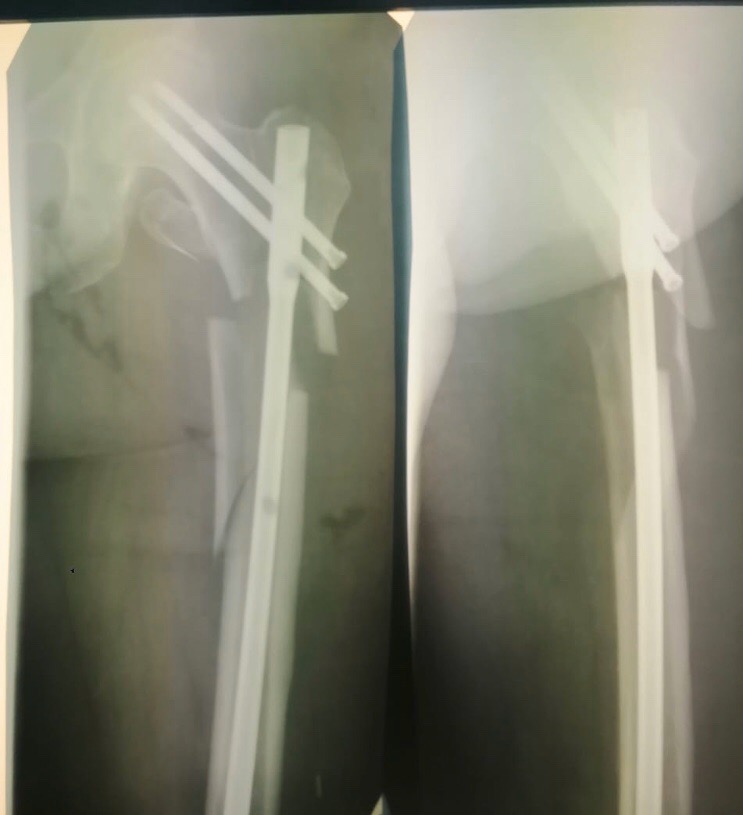

Именно в этот момент встал чёткий вопрос где я в дальнейшем хочу жить и работать и взор мой пал на юг. пережив кучу экзаменов, небодьшие неурядицы с родителями (они то хотели чтобы я вернулся в родной город "Усть-Залупинск) Мы продав всё кроме кошки рванули в Краснодар, да по началу было пиздос как сложно, новое место, новые люди, новая работа которая до сих пор забирает львиную долю моего времени и сил.... Но уж так повелось человек скотина такая ко всему привыкает и вобще всё могло быть гораздо хуже. Тем более мне пока что нравится то чем я сейчас занимаюсь. И как итог всего под самые праздники мне доверили сделать мой первый БИОС бедра, кэшно под строгим контролем старших коллег, но это было восхитительное завершение года.)))